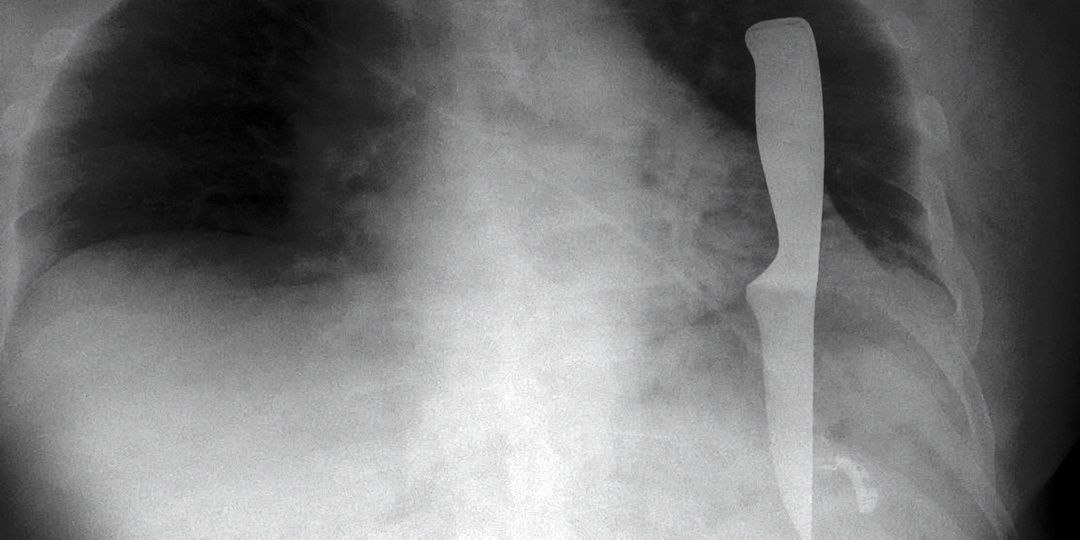

В Первой градской больнице в легком мужчины нашли кухонный нож

В Городскую клиническую больницу №1 имени Н.И. Пирогова поступил мужчина с множественными колото-резаными ножевыми ранениями груди, шеи и предплечья. Врачи экстренно провели рентгенологическое исследование и КТ, которые выявили в левой плевральный полости мужчины инородный предмет — кухонный нож. Врачи впервые столкнулись с такой ситуацией. Еще больше их удивило, что лезвие ножа прошло в нескольких миллиметрах от сердца и не задело его оболочки. Хирурги удалили нож и ушили легкое, которое было повреждено в шести местах. Операцию проводила мультидисциплинарная бригада, которая состояла из хирургов, травматолога и реаниматологов. После вмешательства пациент некоторое время находился под наблюдением врачей, сейчас мужчина уже выписан домой, его жизни ничего не угрожает. Источник информации: Городская клиническая больница №1 имени Н.И. Пирогова